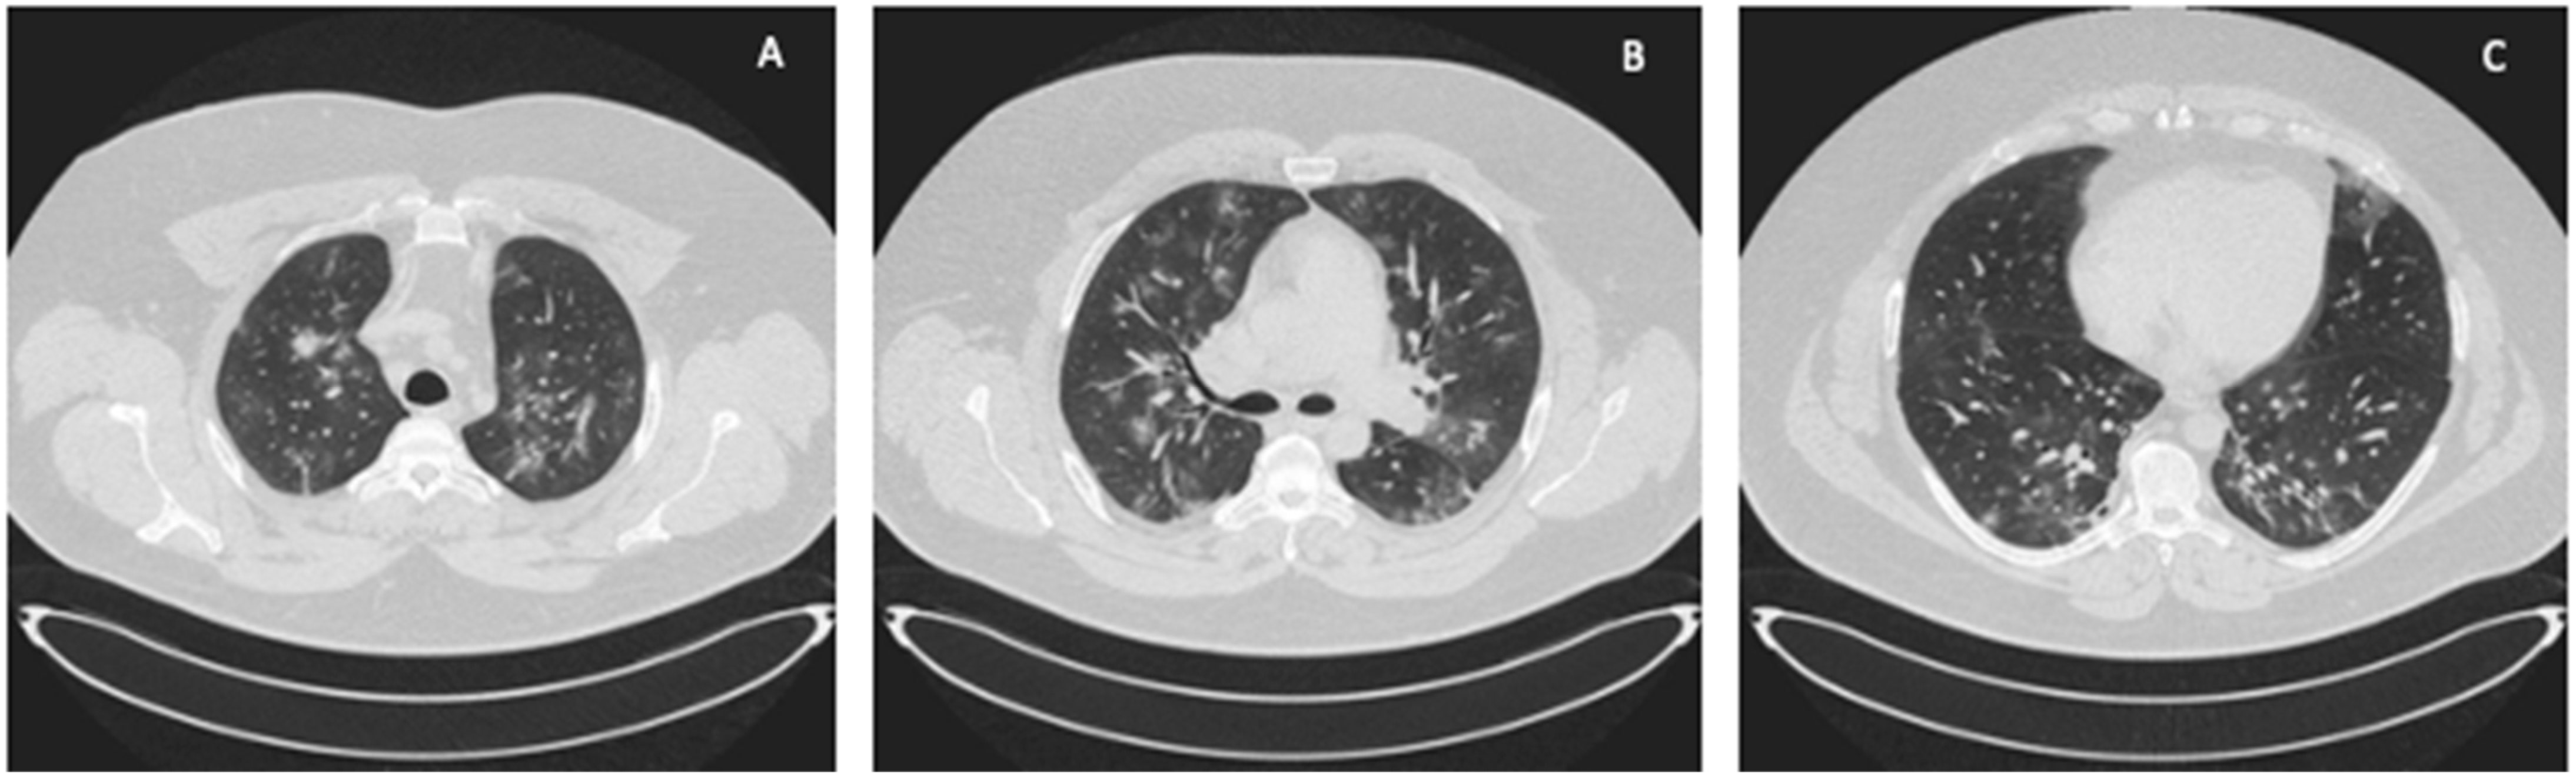

The Seldinger technique was used to place a 15-cm long, 21F-thick BIOLINE-coated Getinge HLS cannula into the superior vena cava through the right internal jugular vein (inflow), and a 65-cm long, 25F-thick BIOLINE-coated Getinge HLS cannula was inserted surgically through the right femoral vein into the inferior vena cava (intake). The surgical technique was applied because of the patient’s significant obesity and the expected technical difficulties in administering femoral vein venipuncture. The correct position of the cannulas was confirmed by ultrasound examination and chest X-ray (Figure 2).

Figure 2. Chest X-ray after insertion of the 21F cannula into the superior vena cava (Case 1).